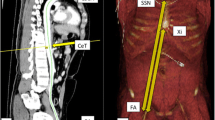

Central luminal line measurement method

The software program 3Mensio Vascular™ (Pie Medical Imaging BV, Maastricht, The Netherlands) was used to create a 3D-reconstruction of the aorta and iliofemoral trajectories and construct a central luminal line (CLL) within this vasculature (Fig. 1). By measuring along the central axis of the aorto-iliofemoral lumen, zone lengths and intravascular distances from the femoral arterial access points (FAAP) to the zone boundaries could be determined. The right and left CFA at the mid-femoral head level were chosen as the FAAP and starting points for the distance measurements [17,18,19, 23]. The REBOA-zones were defined by the major aortic branches which represent the zone boundaries. Zone III length was the distance between the aortic bifurcation (AB, inferior boundary of zone III) and the distal origin of the lowest main renal artery (RA, superior boundary of zone III). Zone II extended from the lower RA to the CT. Zone I ranged from the proximal origin of the CT (inferior boundary of zone I) to the distal origin of the LSA (superior boundary of zone I). Aortic diameters and the depth of the left CFA, defined as the shortest distance from the skin, were also measured. Two authors (JvdV and BV) performed the measurements.

Representative images of the intravascular distances measurement method with a 3D-reconstruction of the aorta and iliofemoral trajectory (a), construction of a central luminal line (b & c) and the stretched vessel configuration in coronal (d) and sagittal (e) anatomical plane with zone III (blue shaded region) and II (orange shaded region). The dotted lines represent the mid-femoral head (red), aortic bifurcation (green), distal origin of lowest renal artery (blue) and proximal origin of celiac trunk (orange) levels